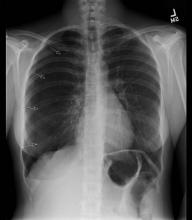

As with any procedure, informed consent is obtained and time-out conducted, including confirmation of identity and laterality with imaging studies (Figure 1 [3]). The site of insertion is the anterior chest wall, mid-clavicular line at the second intercostal space. A routine prep and drape is conducted (Figure 2 [4]). Next, local anesthetic (1% lidocaine) is infiltrated into the anterior 2nd intercostal space, staying just on the superior aspect of the rib. Typically, the authors have done this with local anesthetic (with minimal to no intravenous narcotics), and it is well tolerated (Figure 3 [5]). Once local anesthetic has been infiltrated, the introducer needle and catheter are used to aspirate air as the needle and catheter are advanced into pleural cavity (Figure 4 [6]). Once in the pleural cavity, a flexible guidewire is advanced into the pleural space (Figure 5 [7]). A small skin incision with a #11 scalpel facilitates passage of the dilator and subsequently the drain (Figure 6 [8]). The dilator is slowly advanced over the guidewire just enough to enter the pleural cavity. It is important to always maintain control of the end of the guidewire (Figure 7 [9]). Following dilation, the dilator is removed, and the percutaneous drain is advanced over the guidewire until the holes are all in the pleural cavity (Figure 8 [10]). Once the catheter is in the pleural cavity, tension on the drawstring locks the pigtail catheter. Finally, the pigtail catheter is connected to a Pneumostat valve or other water seal/collection device (Figures 9 [11] & 10 [12]).

Institutional protocols and surgeon preferences may vary; our typical patient care flow is illustrated in the algorithm in (Figure 11 [13]). Once the percutaneous drain is placed, a plain chest radiograph is done. Failure of percutaneous drain placement is corrected with a standard thoracostomy tube. If there is improvement or resolution of the pneumothorax with the percutaneous drain, the patient is discharged home (typically within 12-24 hours). Lung re-expansion and air leak is checked as an outpatient. Successful treatment, defined as re-expansion and no air leak, leads to tube removal in clinic. A persistent pneumothorax or air leak is treated with an additional percutaneous chest drain, or the patient is scheduled for thoracoscopy.